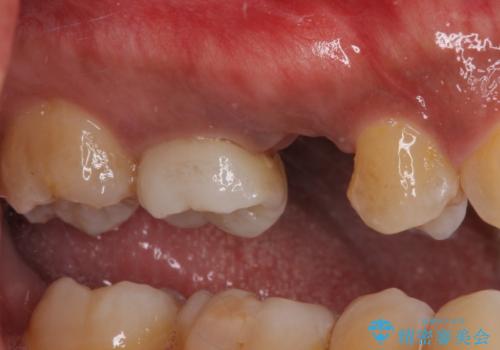

レントゲン撮影により、右上奥歯が折れていることが分かりました。

患者様自身も何となく違和感を覚えていたとのことで、インプラント補綴治療を行うこととしました。

歯列不正は比較的軽微であったので、インビザラインによる矯正治療とし、矯正治療中にタイミングを見て抜歯とインプラント埋入を行う予定としました。